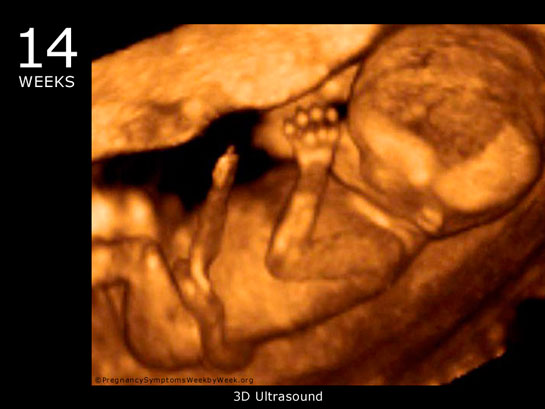

24 Haftalık Gebelik 24 haftalık gebelik, bir hamilelik sürecinin ikinci trimesterinin sonlarına yaklaşan bir dönemi temsil eder. Bu dönem, hem anne hem de bebek açısından önemli fizyolojik değişimlerin yaşandığı bir süreçtir. Bu yazıda, 24 haftalık gebelik döneminde meydana gelen gelişmeler, sağlık önerileri ve dikkat edilmesi gereken noktalar detaylı bir şekilde ele alınacaktır. Fetal Gelişim 24 haftalık gebelikte fetusun gelişimi önemli bir aşamaya ulaşmıştır. Bu dönemde, fetusun boyu yaklaşık 30 cm, ağırlığı ise 600-700 gram civarındadır. Aşağıda, fetal gelişim ile ilgili bazı önemli noktalar belirtilmiştir:

Bebek Gelişimi